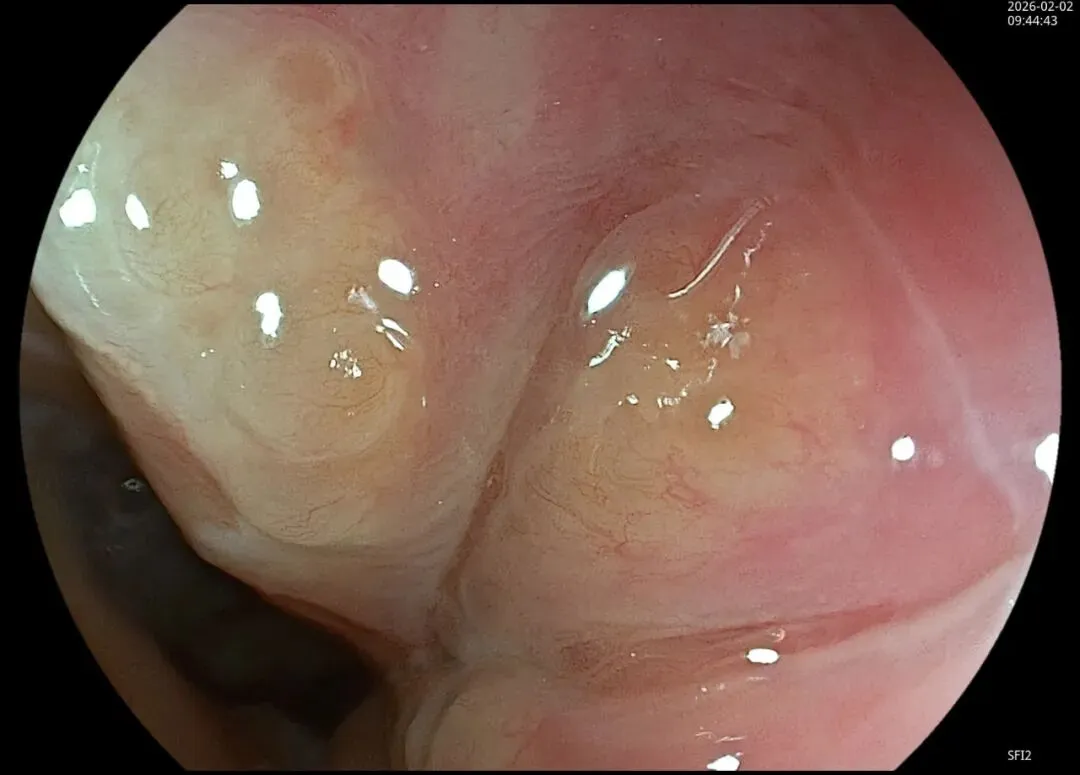

这一期不用码字,挺好的,很可惜一直没机会听过胡导讲的关于这个“花环征”的大课,学习内容来源于雨夜大师的号花环征:AIG背景的胃食管结合部的黄色颗粒状隆起及半透明“泡状”改变

补充自己在两例A型胃炎/AIG 观察到的“花环征”,巩固下学习效果。。。

1.白光表现为胃食管交界处黄色颗粒状隆起及半透明“泡状”改变

2.窄带光下可见颗粒状隆起呈褐色改变,放大可见细微网状血管结构及半透明“泡状”改变

进镜至贲门观察到“花环征”,提示存在AIG的可能,带学生的内镜老师这个moment可以装一把,不过。。。偶尔也有翻车的时候,以下这例是在“Hp现症感染C3萎缩”患者的花环